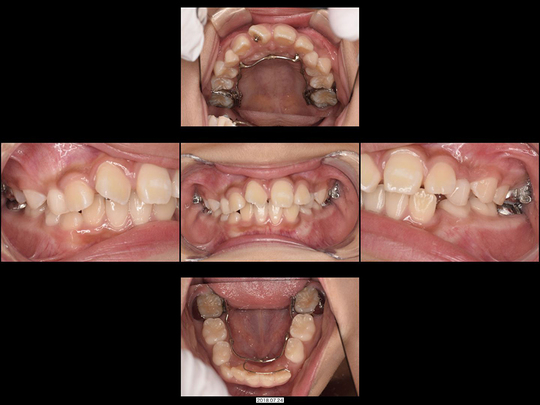

Wさん 開始時8歳 女性

矯正前

矯正治療中

矯正後

前歯がねじれているのを改善したいというご希望でした。「抜歯するしかない」と診断されるような状態です。

固定式の拡大装置を用いて前歯と奥歯の永久歯が生え変わるスペースを作り、正しい歯並びと咬み合わせに誘導(咬合誘導)しました。非抜歯・ワイヤー矯正なしで終了できています。

治療の期間・回数

36か月、36回

​費用

462,000円

リスクや副作用:装置に慣れるまでに1週間ほどかかる可能性があります。歯列を広げる過程で少し痛みを感じる可能性があります。装着時に多少しゃべりづらくなる可能性があります(2~3週間ほどで慣れます)。